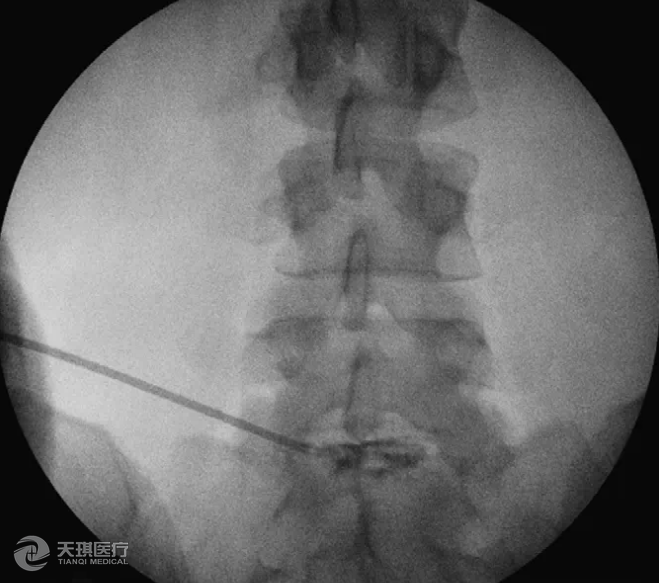

如果患者不能行MRI檢查(例如患者裝有起搏器),CT或脊髓造影可作為替代檢查。椎間盤造影在復雜病例中也可以幫助診斷(圖5)。

圖5 當鑒別腰椎神經根性病變是某個間盤所引起時,椎間盤造影可以幫助診斷。

這個章節(jié)所講的腰椎神經根性病變常見的一個原因就是腰椎間盤突出。目前需要接受手術的腰椎間盤突出使用椎間孔鏡進行治療,創(chuàng)傷小、效果好,是值得優(yōu)先考慮的一種治療方式。